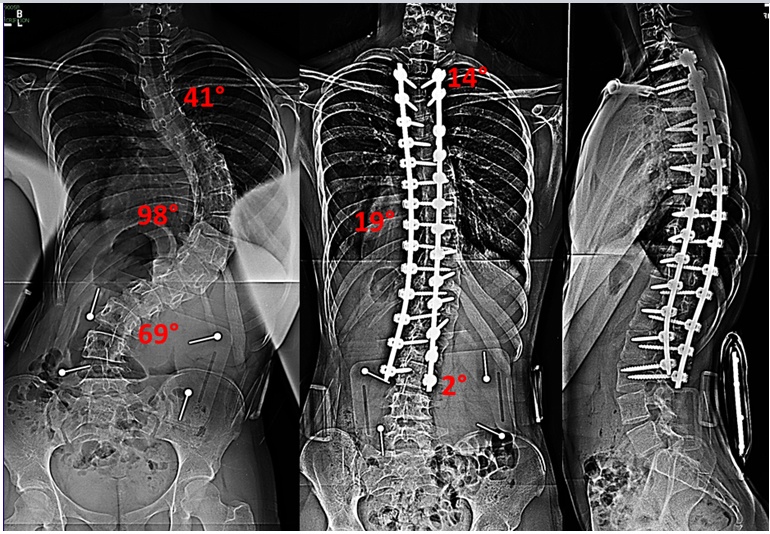

Cobb角大于45°,仍然在进展的脊柱侧弯,或Cobb角大于45°,有并发症的患者。

目前的手术是在脊柱上植入金属材料,然后通过单棒或者双棒进行连接;通过内植物材料矫正脊柱弯曲以及使脊柱维持在矫形的位置,直到脊柱融合为一体。手术可以通过沿后背部一个直切口进行(后路)手术或通过脊柱前方(前路)进行手术。虽然两种入路均有优缺点,但是采用后路手术是目脊柱侧弯手术治疗中最常使用的方法,它可以用于各种类型的脊柱侧凸。前路手术可用于单一的胸段或腰段弯曲的脊柱侧凸患者。手术入路受很多因素影响,医生将进行评估并选择出最佳的方案。

2、关于拍片:3天以后疼痛就会逐渐减轻,手术1周之后疼痛就比较轻微了。术后1周,医生会拍片了解弯曲矫正和内固定的情况,